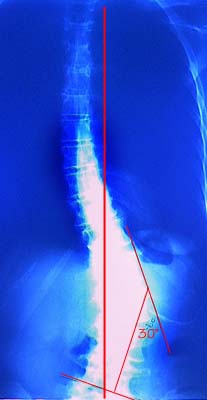

the x-rays of the before and after surgery to photograph, and have posted them

below. I added the red fiducial lines, which are only for reference. The

before x-ray was taken about six months before the surgery. By the time of the

surgery, the displacement angle had increased closer to forty degrees!